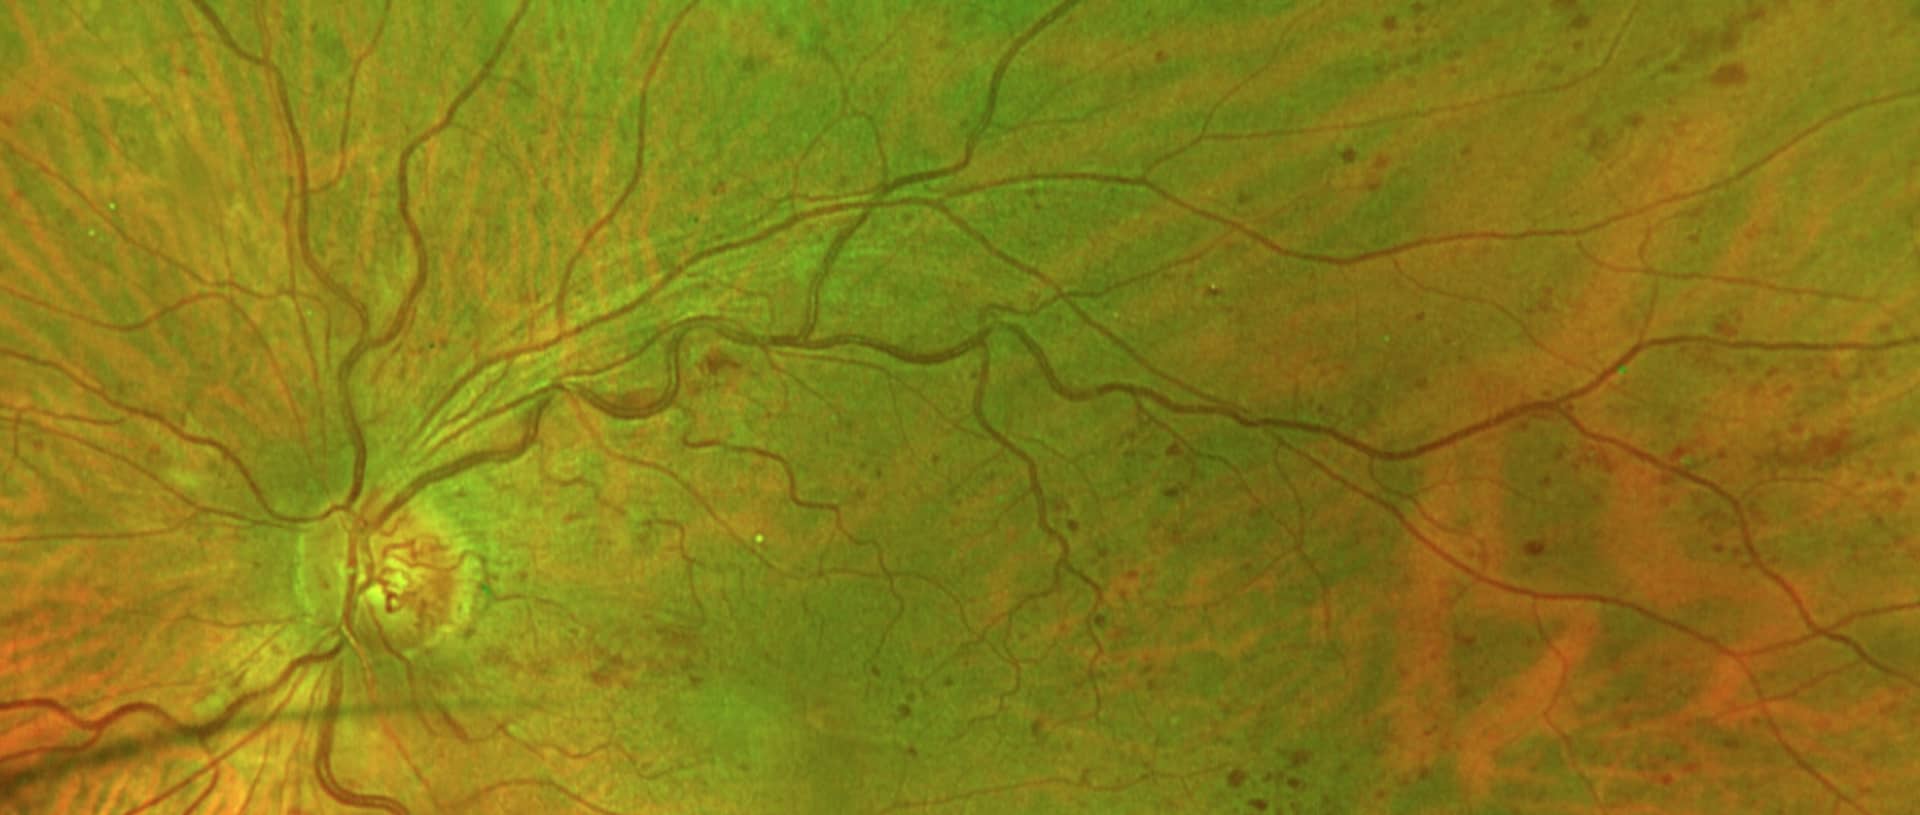

Il s’agit d’une obstruction et/ou un ralentissement du flux veineux soit au niveau du nerf optique (occlusion de la veine centrale de la rétine), soit au niveau d’un croisement artérioveineux (occlusion de branche veineuse rétinienne). Ces deux types d’occlusion diffèrent par le mécanisme physiopathologique. En effet, l’occlusion veineuse centrale de la rétine (OVCR) est dû, supposément, à un ralentissement circulation induisant une thrombose au niveau du tronc veineuse situé au centre du nerf optique. L’occlusion de branche veineuse est causée par un endurcissement d’une artériole au niveau d’un croisement avec une petite veine causant sa compression.

– Baisse d’acuité visuelle unilatérale plus ou moins profonde

– Pas de douleur ni rougeur

Toute baisse d’acuité visuelle brutale unilatérale doit être investiguée rapidement par un ophtalmologue.

Le traitement est variable en fonction de la présentation clinique et oscille entre injections intravitréennes d’anti-VEGF, laser, équilibre des facteurs favorisants et traitement d’un éventuel glaucome